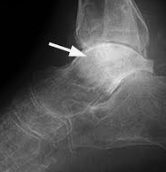

X線写真では骨折線が明らかに認められ、仮骨が非常に少なく、骨の断端は輪郭が不鮮明です。また偽関節では、患部に異常可動性があり、無痛で、X線写真でみると、骨の断端が丸くなっています。

骨髄腔の開口部が閉鎖されている、断端間に輪郭の明瞭な間隙がある、断端の骨の陰影は濃いが、そこから少し離れた部位の陰影は薄く、無機質が減少している、骨折部で骨が屈曲している、などの所見があり、再手術によらないかぎり治癒の可能性がない。